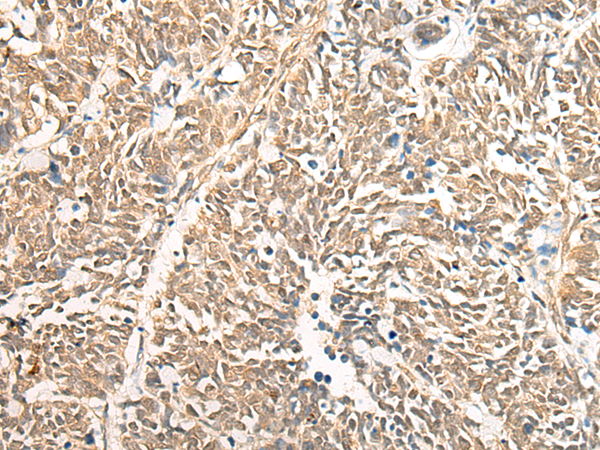

分类: 科研抗体货号: P06380别名: RRP44; dis3p; EXOSC11; KIAA1008; 2810028N01Rik应用: IHC反应种属: Human